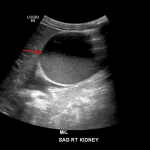

Indication: Abdominal pain

Findings

- Severe right hydronephrosis with echogenic material layering in the right renal pelvis and calyces

- Urothelial thickening of the right renal collecting system

- Increased echogenicity of the right renal parenchyma

- Normal appearance of the left kidney

- Urinary bladder is incompletely distended but otherwise normal in appearance

Diagnosis

Pyonephrosis

Severe right hydronephrosis with urothelial thickening and echogenic material layering in the right renal pelvis and calyces, concerning for pyonephrosis. Recommend urology evaluation.

Increased echogenicity of the right renal parenchyma is suggestive of associated pyelonephritis.

Normal appearance of the left kidney and urinary bladder.